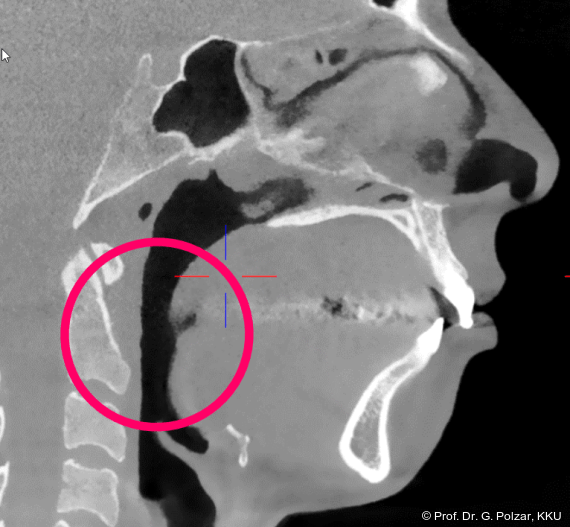

KG-Position: Die 3D-Ansicht im DVT zeigt eine vorverlagerte UK-Position bei neutraler Okklusion (Abb. 4a+b).

Im Sagittalschnitt zeigen beide Kiefergelenke eine deutlich anteriore Position. Der dorsokraniale Abstand betrug rechts 7,0 mm und links 5,8 mm. In der PEP waren sie im lateralen Bereich ca. 1 mm kleiner als in der Mitte der Sagittalprojektion (Abb. 6a–d).

Diese deutlich anteriore Gelenkposition im Neutralbiss ließ den Verdacht auf einen Sunday Bite zu. Das heißt, die Patientin schob den Unterkiefer aktiv nach vorne, um damit schönere Schneidezahnkontakte bzw. eine vermeintlich neutrale Okklusion zu erreichen. Nach mühsamen Lockerungsübungen gelang es der Patientin, auch in die zen­trale Kiefergelenkposition zu wechseln. So zeigte sich das ganze Ausmaß der Malokklusion. In neutraler KG-Position hatte die Patientin eine sagittale Frontzahnstufe von ca. 7 mm mit 1 PB Klasse II-Okklusion im Seitenzahn­bereich (Abb.5a+b, 7a–c).